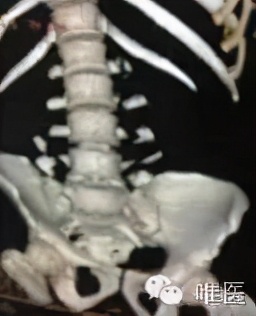

患者男性,26岁,高处坠落伤,腰骶部被厚重的铁门砸伤。

▼ 术前照片